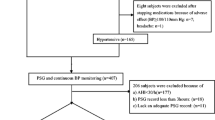

A total of 217 subjects with suspected sleep-disordered breathing were recruited were recruited at our sleep center between March 2016 and April 2017 following an overnight PSG examination. Four patients were taking antihypertensive drugs. To avoid a drug effect on the results, they were instructed to stop treatment 3 days prior to enrollment, and their BP was closely monitored (three cuff measurements on two separate occasions) after resting seated for ≥ 5 min. Individuals whose BP was consistently ≥ 180/110 mmHg or who complained of dizziness, headache, palpitations, and other clinical syndromes were excluded from the protocol, placed back on their BP medications, or given clinical intervention immediately. Patients between 18 and 75 years of age with BP ≤ 180/110 mmHg and with newly diagnosed OSAS or with OSAS without treatment were eligible. Patients who had been hospitalized for cardiac or respiratory exacerbations less than 6 weeks previously; those with autonomic nervous system diseases or with endocrine disorders (that might influence BP variability); or who were unwilling to participate in the study were excluded. In total, 104 patients were enrolled and diagnosed with mild (AHI 5–14, n = 33); moderate (AHI 15–29, n = 34), or severe (AHI ≥ 30, n = 37) OSAS. Figure 1 displayed a flowchart of study design and process. The study was approved by the Scientific Research and Technology Ethics Committee of Huai’an First People’s Hospital (IRB-KPJ 2016–005-01) and registered in ClinicalTrials.gov. (ID: NCT02876471); all subjects gave their informed consent.